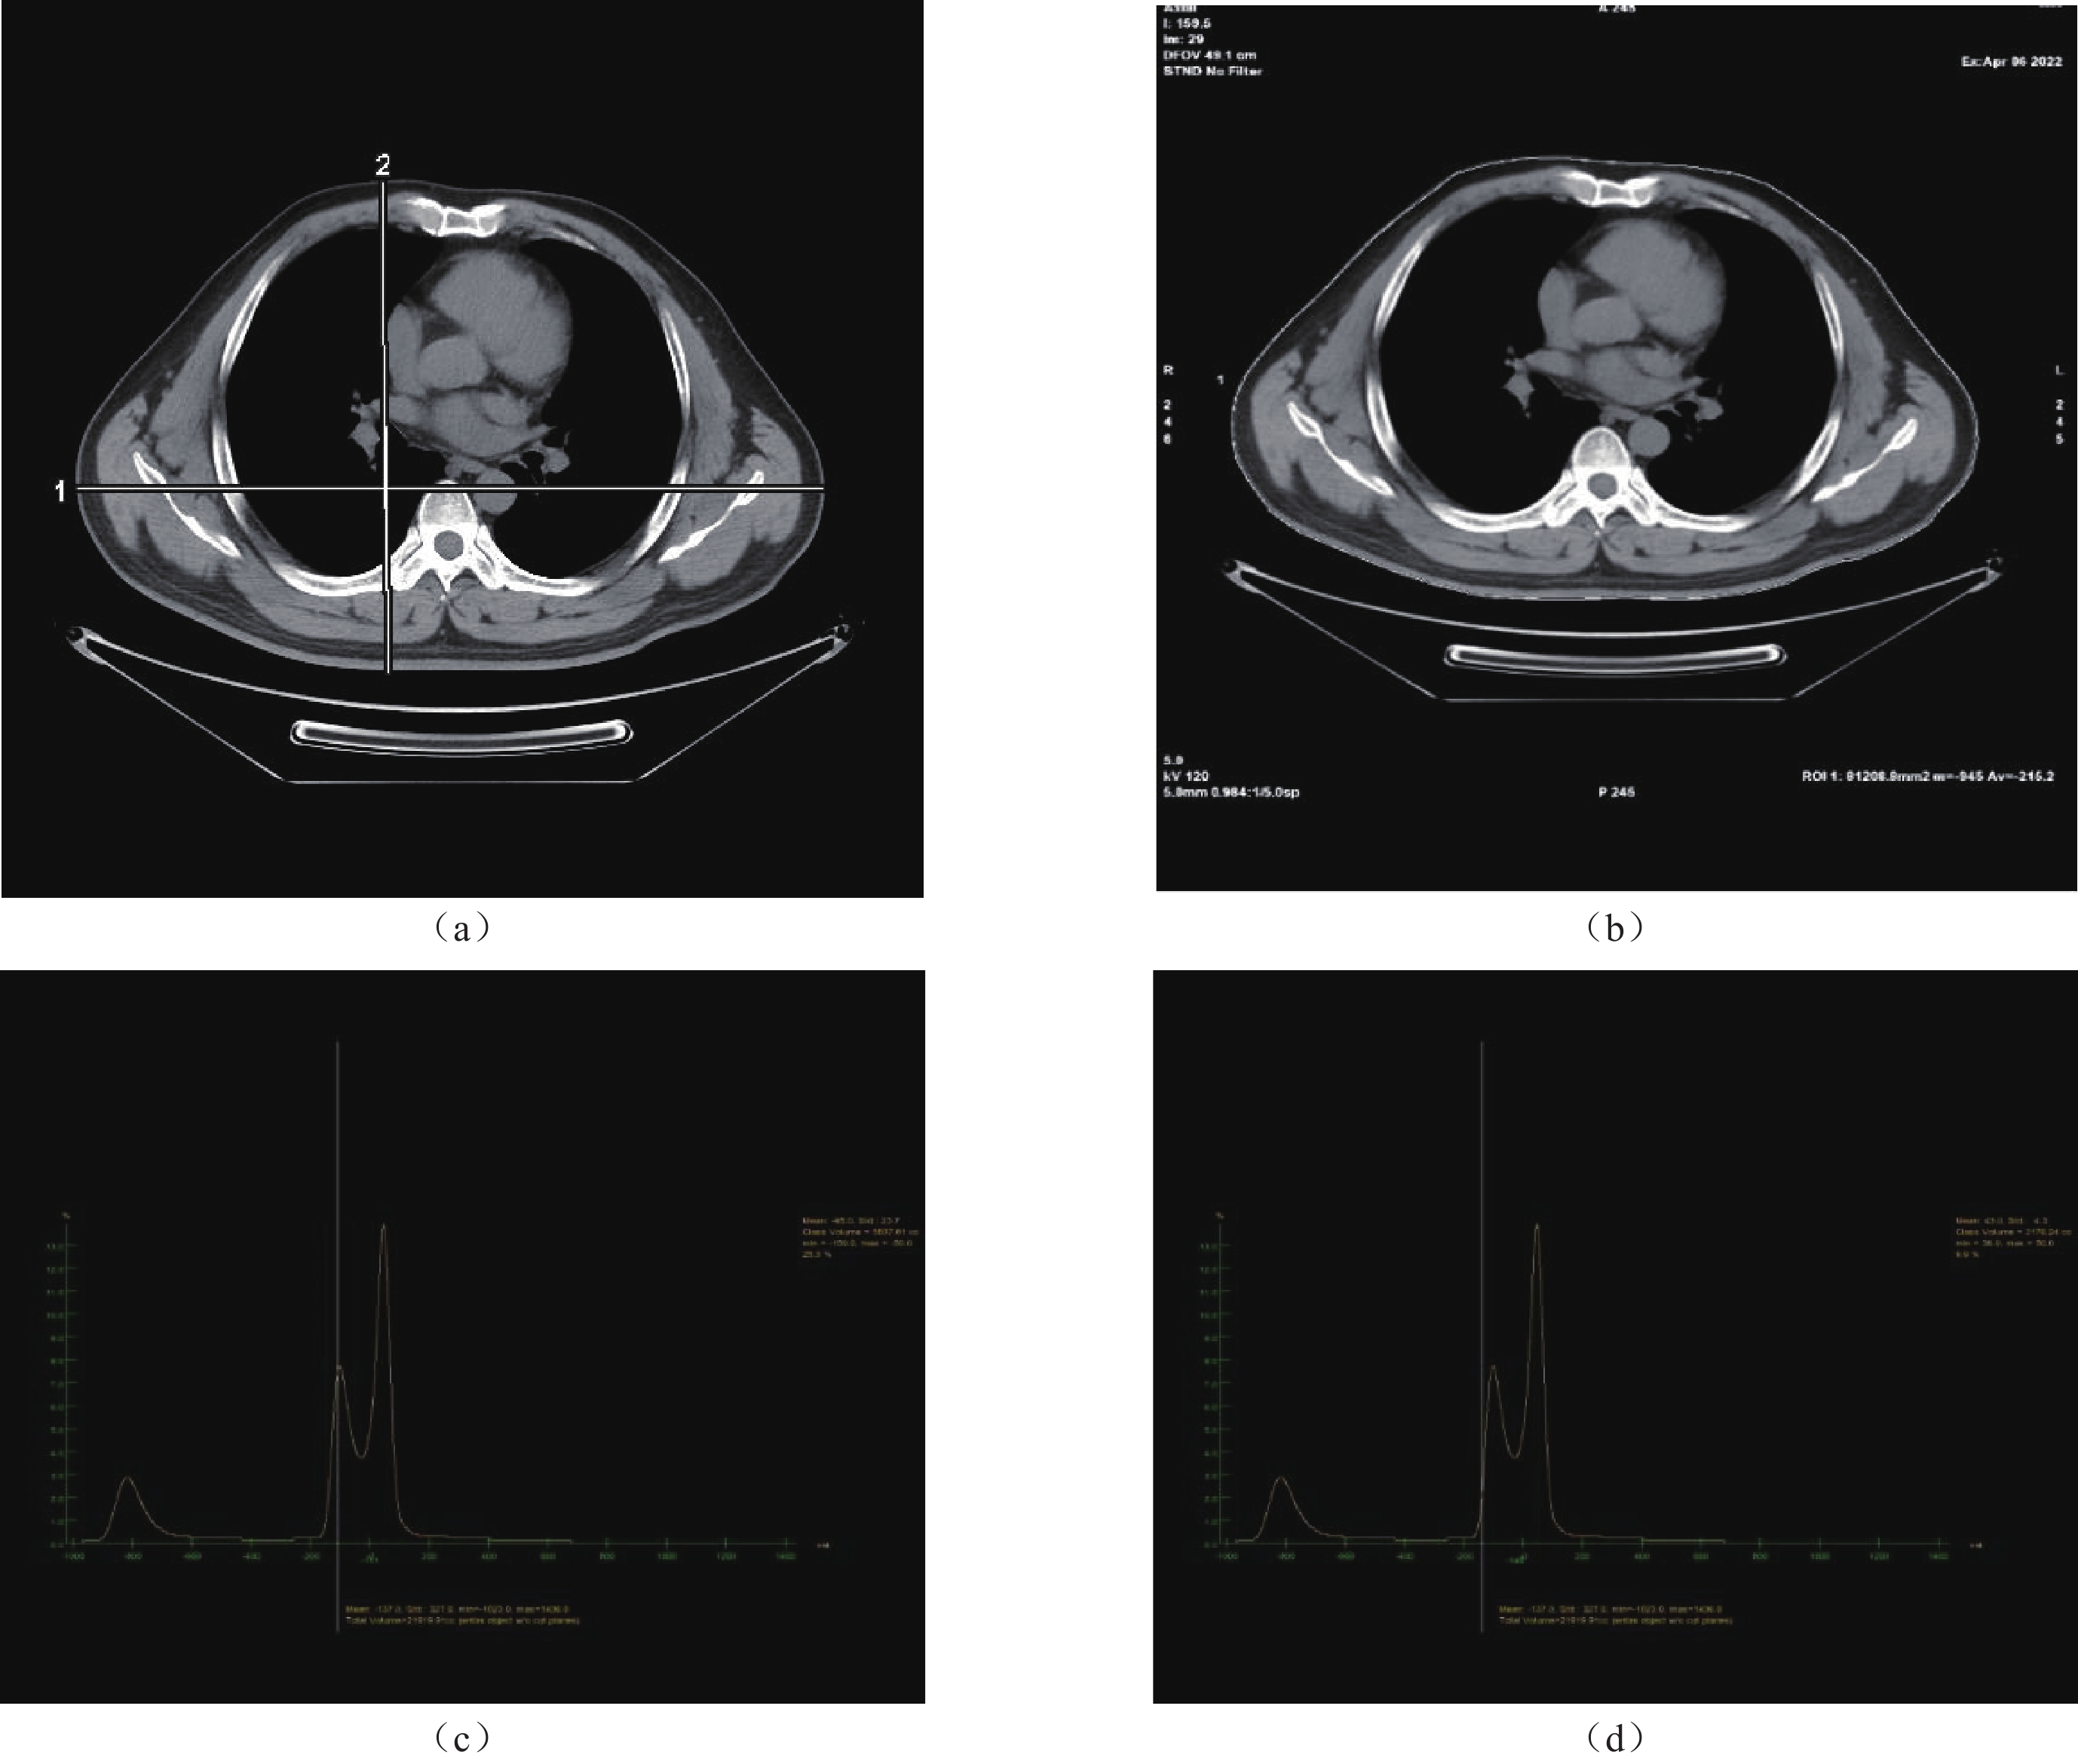

• 摘要: 目的:探讨个体的体型因素及组织成分对成人胸部水当量直径的体型特异性剂量估算(SSDEWED)的影响。方法:收集在本院行胸部CT平扫的成人受检者205例,采集其个体信息(身高、体重、身体质量指数);在中间层面的横断位图像上测量胸廓的平均CTROI值、横断面积AROI、横径、前后径;测量整个扫描范围的脂肪含量、脂肪体积和肌肉含量、肌肉体积;计算前后径/横径、扫描长度、扫描长度/横径;获取受检者的容积CT剂量指数(CTDIvol),计算出所有受检者中间层面的SSDEWED的数值。分析脂肪含量、肌肉含量、脂肪体积、肌肉体积、BMI、横断面AROI、横径、前后径、扫描长度、扫描长度/横径比、前后径/横径比与SSDEWED的相关性。结果:脂肪含量、脂肪体积、肌肉体积、BMI、横断面AROI、横径、前后径、扫描长度/横径比与SSDEWED有显著正相关性;肌肉含量、前后径/横径比值、扫描长度与SSDEWED无相关性。结论:多种个体体型因素及组织成分与SSDEWED有显著相关性,其中脂肪组织是影响SSDEWED的关键的因素。

Abstract: Objective: To investigate the impact of individual body size factors and tissue composition on the size-specific dose estimate(SSDEWED) based on water equivalent diameter for adult chest. Methods: A total of 205 adult subjects who underwent chest CT scans at our hospital were enrolled, and their individual information (height, weight, body mass index) was collected. The average CTROI value, cross-sectional area AROI, transverse diameter, and anteroposterior diameter of the thorax on the axial images at the intermediate level were collected. The fat content, fat volume, muscle content, and muscle volume across the entire scanning range were recorded. The anteroposterior diameter/transverse diameter, scan length, and scan length/transverse diameter were calculated. The volume CT dose index (CTDIvol) of the subjects was obtained, and the SSDEWED values at the mid-level of all subjects were calculated. The correlations between fat content, muscle content, fat volume, muscle volume, BMI, cross-sectional AROI, transverse diameter, anteroposterior diameter, scan length, scan length/transverse diameter ratio, anteroposterior diameter/transverse diameter ratio, and SSDEWED were analyzed. Results: Fat content, fat volume, muscle volume, BMI, cross-sectional AROI, transverse diameter, anteroposterior diameter, scan length/transverse diameter ratio are significantly positively correlated with SSDEWED. Muscle content, anteroposterior/transverse diameter ratio, and scan length showed no correlation with SSDEWED. Conclusion: Multiple individual body size factors and tissue compositions are significantly correlated with SSDEWED, among which adipose tissue is the key factor influencing SSDEWED.